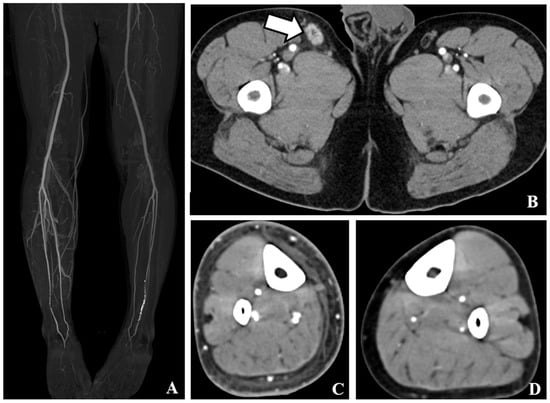

| Venous early return on MIP | 82.8 [77.0–87.9] | 86.9 [80.8–92.3] | 70.5 [56.8–84.1] | 0.012 |